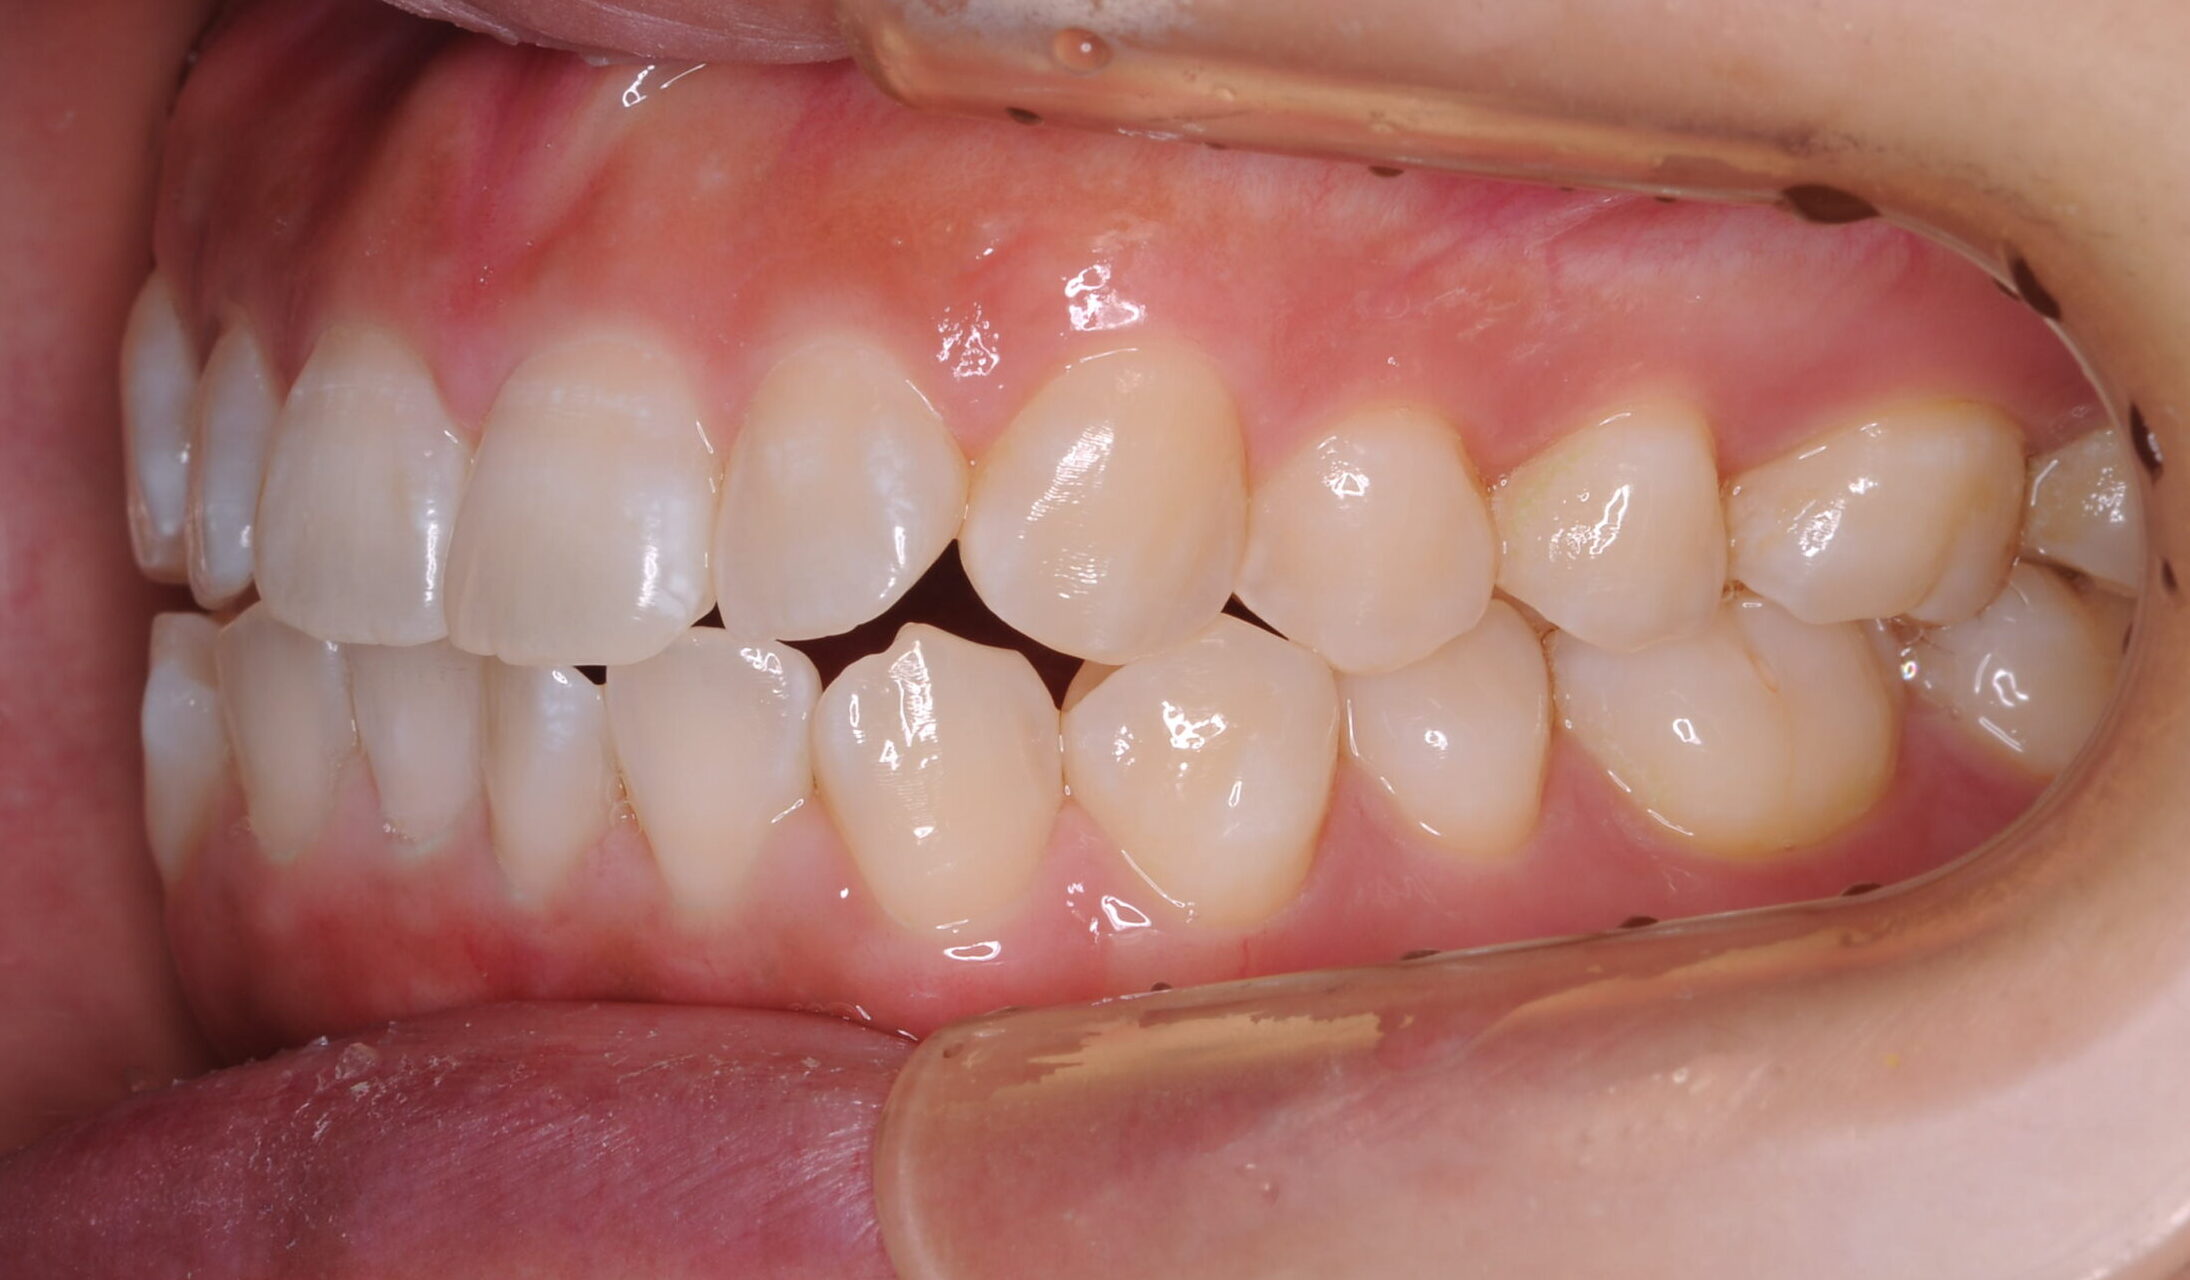

症例写真 after